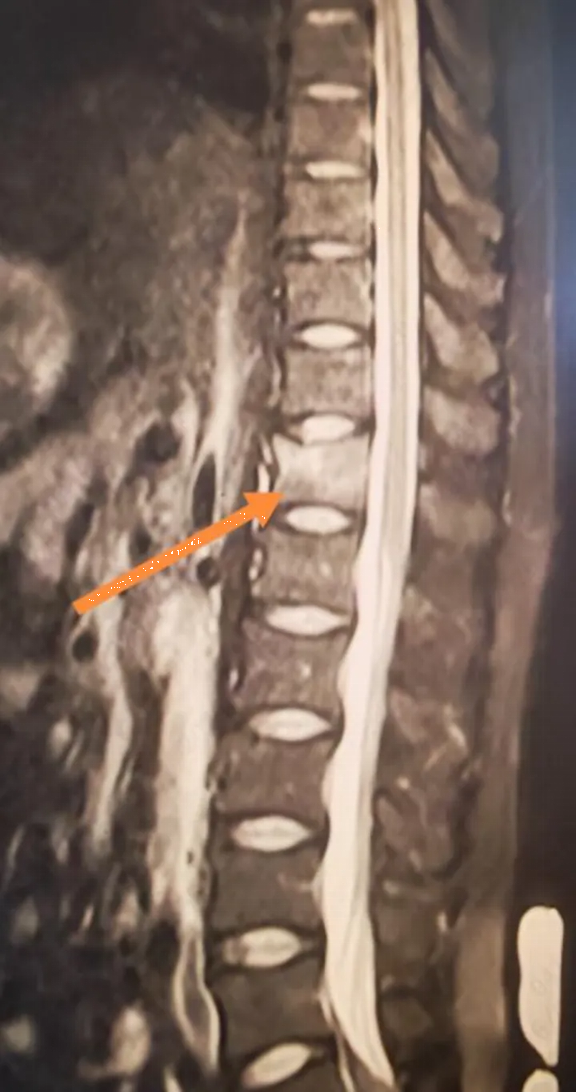

Kết quả chụp MRI khiến anh hoàn toàn sững sờ: gãy xẹp đốt sống T12.

Các xét nghiệm tiếp theo cho thấy kết quả còn gây sốc hơn chỉ số Z-score L1-L4 của anh Lý chỉ là -3,1, nghĩa là mật độ xương của anh thấp hơn so với hầu hết phụ nữ 60 tuổi. Một loạt các xét nghiệm đã loại trừ khả năng loãng xương thứ phát. Kết quả xét nghiệm cho thấy nồng độ vitamin D của anh Lý chỉ ở mức 10 ng/ml, thấp hơn nhiều so với tiêu chuẩn bình thường.

May mắn thay, tình trạng gãy xẹp đốt sống của anh không nghiêm trọng. Bác sĩ đã kê đơn cho anh nằm nghỉ ngơi tuyệt đối trên giường trong một tháng, yêu cầu anh đeo đai hỗ trợ thắt lưng y tế hàng ngày và bổ sung đủ canxi, vitamin D cùng thuốc chống loãng xương.